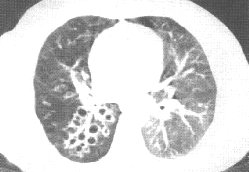

支氣管擴張另外,需要引起注意:小兒胸部X線檢查所見,隨呼吸相而不同,胸部各器官和組織形態均隨呼吸相而產生相應的變化。在呼氣相,膈肌上升,肺血管充血,縱隔增寬遮蓋肺臟,使肺野面積大為縮小。因此,拍胸片時,應有合適程度的吸氣,以免與其他疾病混淆。並儘可能採用坐或站立後前位,這樣能使膈肌下降,縱隔投照放大率較小。